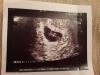

Девочки, у кого есть фото с узи 5-6 недель, отправьте пожалуйста🌹

Это 6ая неделя 🌝

В левом углу общая картинка

На таком сроке бывает видно только колечко с "бриллиантом" 🤗

на 5-6 неделе только черное пятно бывает) у меня 8 недель есть